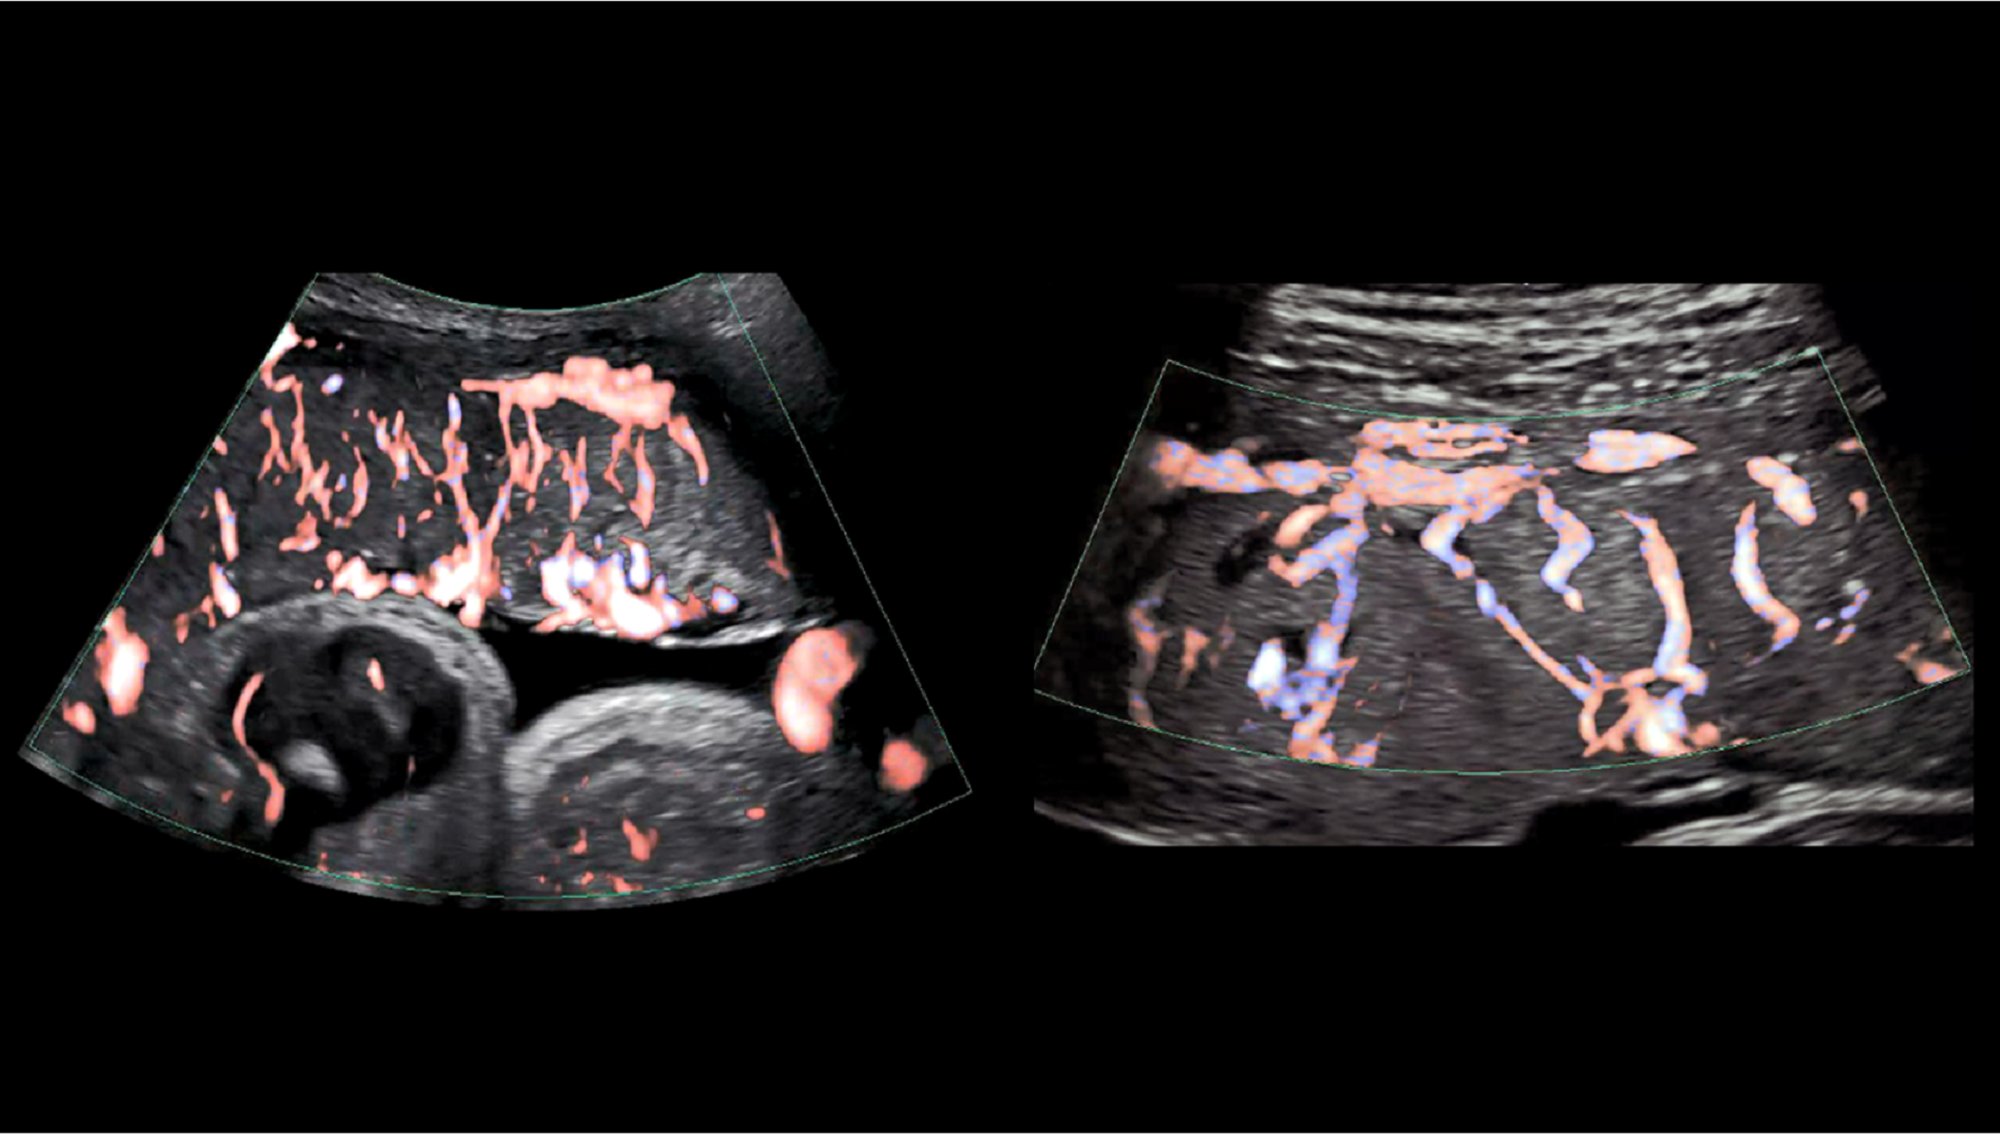

Ultrasound images showing placenta tissues from a fetus (left) and a pregnant person's uterus (right). In general, the placenta is hard to study in the early stages of pregnancy. Eastern Virginia Medical School and University of Texas Medical Branch

But beyond the essentials, experts know very little about how the placenta develops and operates. In a recent blog post, Diana W. Bianchi, a senior investigator at the National Institute of Health (NIH), wrote that the placenta is “the least understood, and least studied organ.” She then explains how developing better ultrasound and MRI imaging techniques can help doctors study the placenta during pregnancy, work that the Eastern Virginia Medical School and University of Texas Medical Branch have used to study placental vasculature, as shown above.